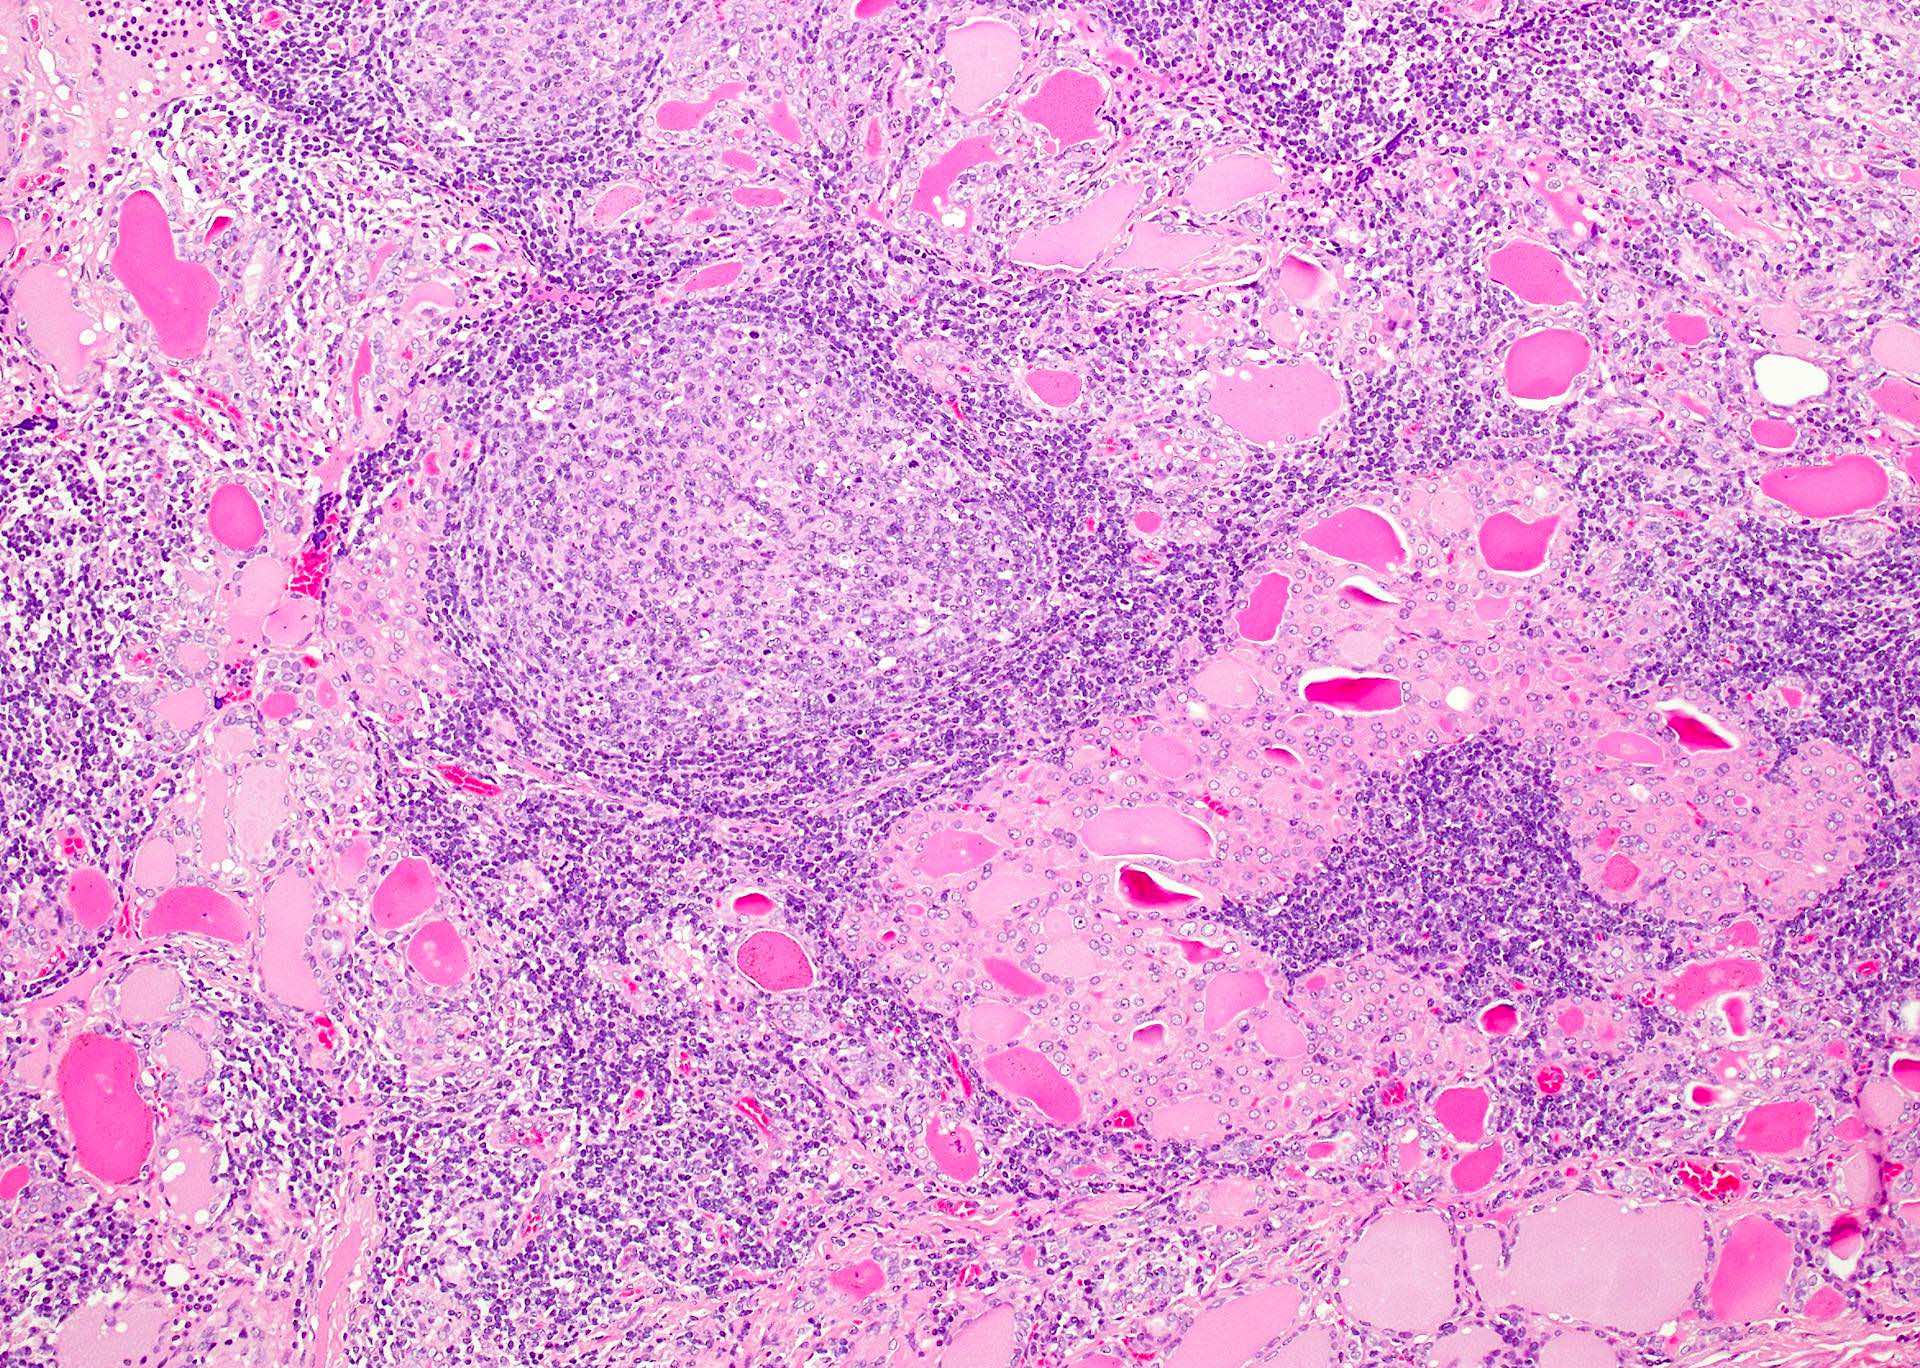

Microscopic (histologic) description

- Classic form: diffuse infiltration of thyroid parenchyma with lymphocytes and plasma cells; lymphoid follicle formation with germinal centers (Best Pract Res Clin Endocrinol Metab 2019;33:101367)

- Polymorphic lymphocytic infiltrate, predominantly T cells

- Thyroid follicular destruction

- Atrophic thyroid follicles; many lined by oncocytic cells / oncocytes having abundant granular eosinophilic cytoplasm; rarely squamous metaplasia

- Later fibrosis and nodularity (Virchows Arch 2013;462:557)

- Fibrous (or fibrosing) variant: extensive keloid-like fibrosis of thyroid parenchyma, fibrous septa divide the parenchyma into lobules, mononuclear cell infiltration, lymphoid follicles, thyroid follicular atrophy, oncocytic cell and squamous metaplasia (Autoimmun Rev 2014;13:391)

- IgG4 related variant: dense lymphoplasmacytic infiltrate, enriched in IgG4 producing plasma cells (> 20 cells per high power field); interstitial fibrosis; often associated with obliterative phlebitis (Autoimmun Rev 2014;13:391)

- Juvenile thyroiditis, Hashitoxicosis and painless thyroiditis: rare / absent germinal center formation and follicular atrophy, follicular cell hyperplasia, less pronounced oncocytic cell metaplasia and fibrosis (Autoimmun Rev 2014;13:391)

- Variable atypia of follicular cells and oncocytic cells, may mimic and act as a precursor (limited evidence) of papillary thyroid carcinoma (Endocr Pathol 2021;32:368)

- Squamous metaplasia of follicular epithelium can be confused with solid cell nests (J Clin Endocrinol Metab 2012;97:2209)

- May be associated with colloid goiter, follicular neoplasm, oncocytic cell neoplasm, papillary thyroid carcinoma and primary thyroid lymphoma (Acta Cytol 2009;53:507, Front Oncol 2017;7:53)

Microscopic (histologic) images

Contributed by Andrey Bychkov, M.D., Ph.D. and Shipra Agarwal, M.D.